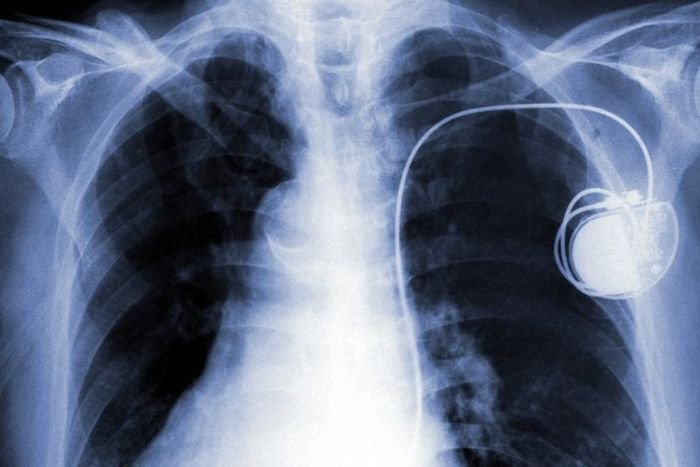

Сложившаяся в последние годы ситуация вокруг обеспечения кибербезопасности взволновала не только мировые правительства, но и медиков. Врачи всерьез опасаются возможной волны хакерских атак, направленных на взлом различных имплантированных в тело устройств – от инсулиновых помп до кардиостимуляторов. Сегодня все больше медицинских клиник предлагают своим пациентам вживление под кожу различных медицинских приборов для уменьшения риска фатального исхода в критической ситуации. В первую очередь речь идет о людях, которые испытывают серьезные проблемы с сердечнососудистой системой, а также страдающих диабетом.

Некоторые медики считают, что вживление в человеческое тело различных чипов, следящих за состоянием здоровья, может приобрести со временем глобальный масштаб. Врачи всерьез обеспокоены возможностью обратного эффектаданной терапии. Для наглядности можно привести пример из киноиндустрии, а именно эпизод из сериала Homeland, в котором вице-президент США гибнет от успешной атаки хакеров на его кардиостимулятор. Хакеры взломали кардиостимулятор и пустили от него разряд электричества в тело вице-президента.

На сегодняшний день уязвимости были обнаружены в отдельных кардиостимуляторах и инсулиновых помпах, которые уже вживляются пациентам клиник. В рамках проведенного исследования ученым удалось изменить через радиоканал режим работы инсулиновой помпы, которая содержала 300 доз инсулина, таким образом, что пациент за один раз получал все дозы, которые были рассчитаны на курс в 1,5 месяца. Такая передозировка стала бы причинойгарантированной смерти. Хотя такого рода устройства и оснащаются некоторыми системами защиты, хакеры смогли бы ее отключить.